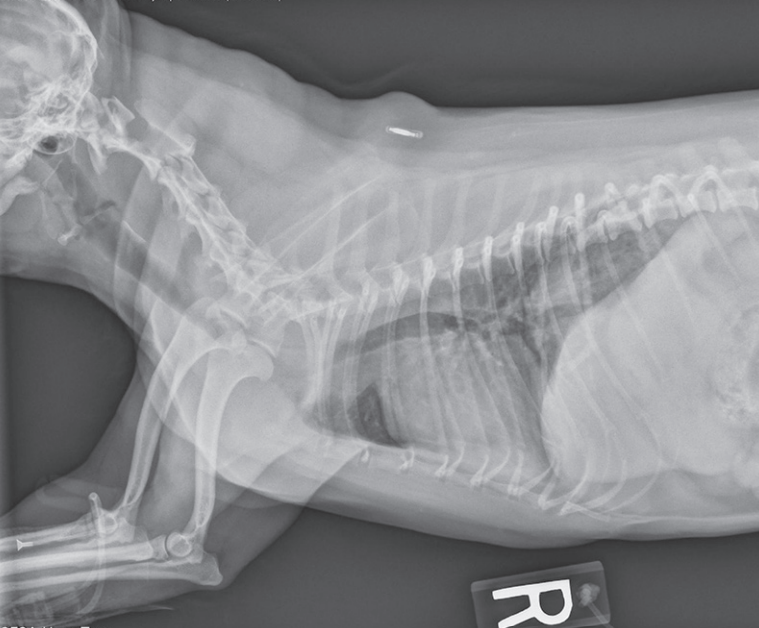

臨床檢查:狗狗明顯喘不過氣,呼吸速率為每分鐘 60 下,伴隨明顯的上呼吸道喘鳴與鼾聲,並不時咳嗽。體溫為 39.9°C,心跳為每分鐘 160 下,黏膜呈現暗淡或發紺的顏色。由於懷疑是氣管塌陷,我們安排了胸部X光檢查。

胸部X光檢查:小米的頸部與胸前段氣管有明顯狹窄現象,與氣管塌陷的典型影像相符。綜合牠的臨床症狀與影像結果,我們診斷小米為氣管塌陷(第三級到第四級)。